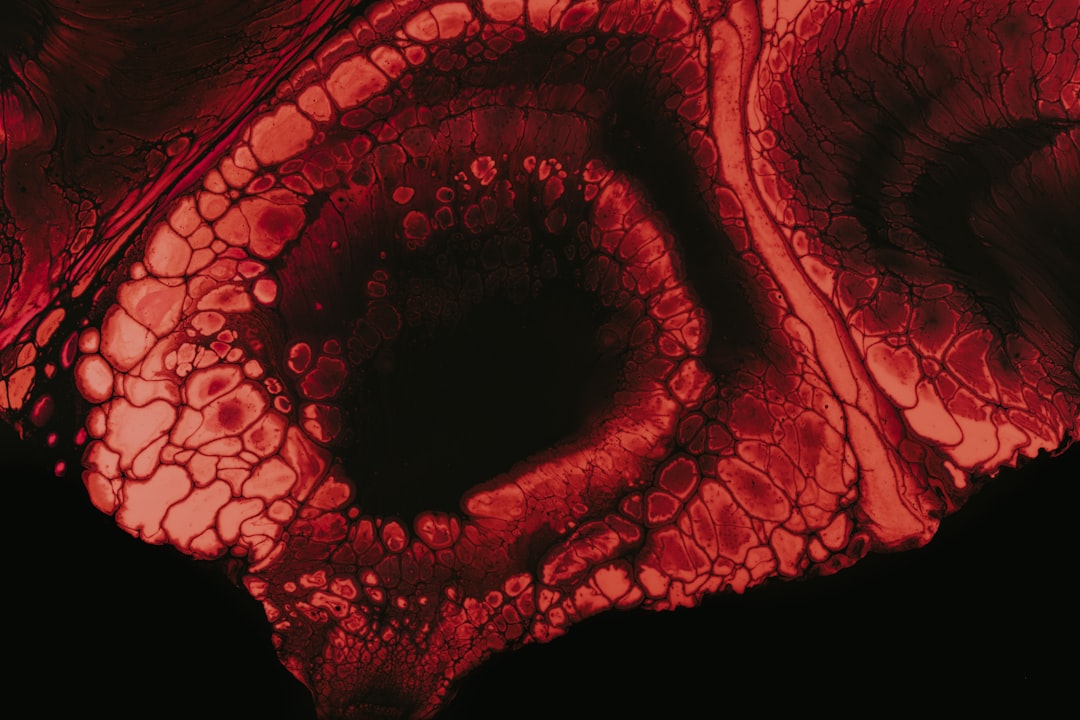

대장암은 우리 몸의 소화기관 중 하나인 대장에서 발생하는 암으로, 조기 발견이 핵심입니다. 대장암 의심 증상? 초기 증상부터 알아보자라는 주제로 이야기해보겠습니다. 대장암이 발생했을 때, 초기에는 뚜렷한 증상이 나타나지 않을 수 있습니다. 하지만 몇 가지 신호를 통해 조기에 발견할 수 있으며, 이를 통해 생존율을 높일 수 있습니다. 이러한 신호는 흔히 무시되기 쉽기 때문에 주의 깊게 살펴보아야 합니다.

대장암 의심 증상으로는 다른 증상들도 다양하게 존재합니다. 이러한 증상들은 보통 대장 내에서의 이상 소견을 바탕으로 합니다. 간혹 대변에 혈액이나 점액이 섞여 나오는 경우가 있는데, 이것은 결코 가벼운 증상이 아닙니다. 실제로 제 주변에서 이러한 증상을 겪었던 지인이 있었는데, 초기 검사로 인해 조기에 대장암이 발견되었습니다. 모두가 이처럼 본인에게 소중한 시간을 소홀히 하지 않도록 하길 바랍니다.